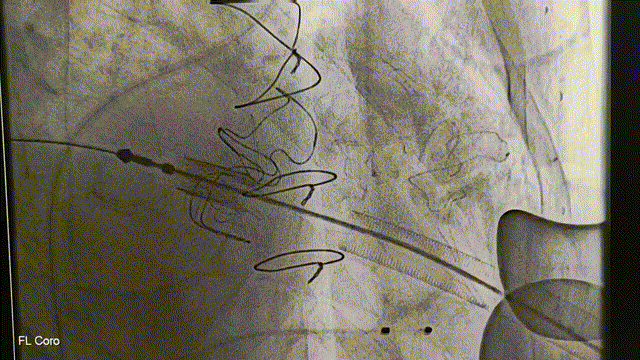

冠脉造影:左主干未见明显狭窄,前降支未见明显狭窄,血流TIMI3级,回旋支中段约40%狭窄,血流TIMI3级,右冠状动脉中段远段闭塞,血流TIMI0级。

DSA引导下定位心尖,心尖穿刺后置入泥鳅导丝及导管。利用导丝导管配合,穿过二尖瓣生物瓣。通过二尖瓣后置换加硬导丝。沿加硬导丝,置入J-Valve植入器。术中,通过观察定位件跳动的形态判断瓣膜位置,同时可以清晰感觉到力的反馈。定位件稳稳锚定原瓣架,可看到三个定位件随着心脏搏动而自然摆动。确定好位置后释放瓣膜,锁丝脱钩,瓣膜与植入器完全分离。观察瓣周漏与瓣膜形态,经食管超声心动图显示瓣膜位置合适,形态良好,无瓣周漏和反流。